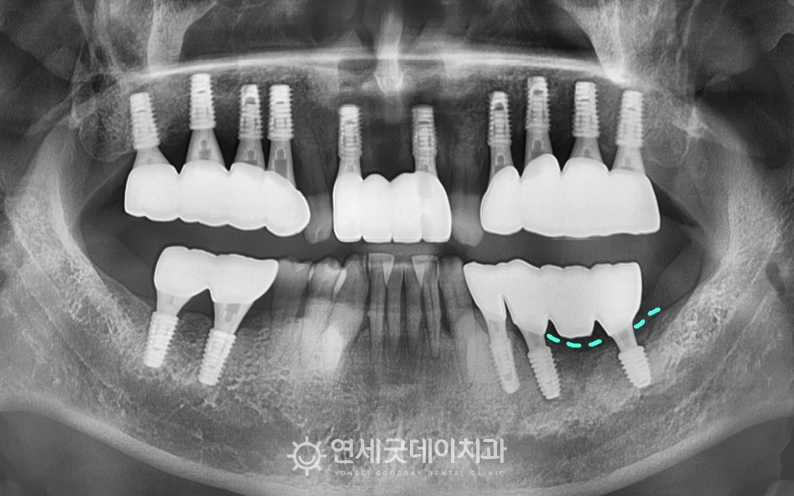

엑스레이를 보면 #35 부위에 치근단 병소가 확인되었고,

치근단염이 관찰되었던 #35 부위를 발치 및 제거 후에는 추후 새로운 임플란트를 안전하게 심고,

치료전과 후를 보시면 완전히 내려 앉았던 잇몸뼈가